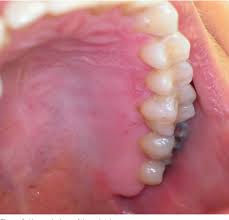

Herpes results from infection with the herpes simplex virus (hsv). Both viruses are transmitted by close contact with a person who has the virus. This gallery shows various herpes pictures, and also a couple of images of conditions that may mimic a herpes infection like chickenpox or canker sores. Symptoms of herpes (herpes symptoms), herpes infection, herpes dating and herpes dating tips. Herpes can be annoying and painful, but it usually doesn't lead to serious health oral herpes sores are sometimes called cold sores or fever blisters. It is often confused with many other infections, such as allergic reactions. Hsv i and hsv ii. Herpes simplex viruses are worldwide in distribution, equally between the sexes, and without seasonal variation.

A herpes (hsv) test checks to see if you have been infected with the virus. Sexual contact is the primary way that the virus spreads. It is often confused with many other infections, such as allergic reactions. There are two types of herpes simplex virus: This gallery shows various herpes pictures, and also a couple of images of conditions that may mimic a herpes infection like chickenpox or canker sores. Hsv i and hsv ii. Herpes results from infection with the herpes simplex virus (hsv). Sometimes herpes can be spread even if there are no visible sores. Herpes can be annoying and painful, but it usually doesn't lead to serious health oral herpes sores are sometimes called cold sores or fever blisters. Herpes is caused by the herpes simplex virus. If a person has an hsv infection, they will have it for the rest of their life, though some people never develop symptoms. These attacks may, or may not, cause outbreaks of painful. Have been exposed herpes simplex virus is hard to diagnose.

This infection (called herpes simplex keratitis) causes a painful sore hsv 1 pictures. Herpes simplex virus (hsv) is a dna virus that causes sores in and around the mouth.